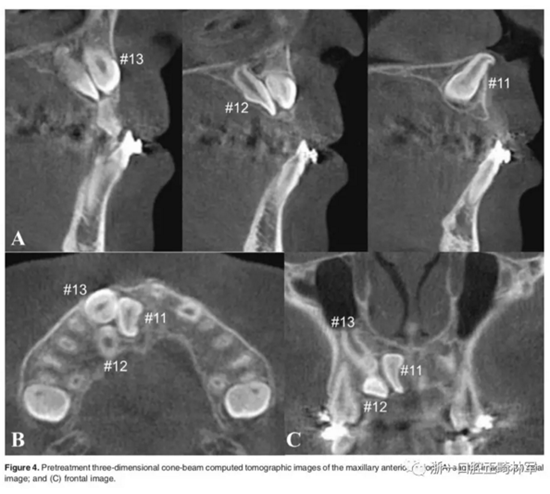

影像檢查:

全景X片及CBCT示:11-13復(fù)雜阻生,上頜前牙區(qū)牙槽骨水平不足;11阻生,遠(yuǎn)中旋轉(zhuǎn)90°,牙冠朝向腭側(cè),根尖位于鼻底、前鼻棘皮質(zhì)骨內(nèi),牙根形態(tài)彎曲;12、13不完全易位,12位置偏腭側(cè),13位置偏舌側(cè),12的牙根形態(tài)也較彎曲。